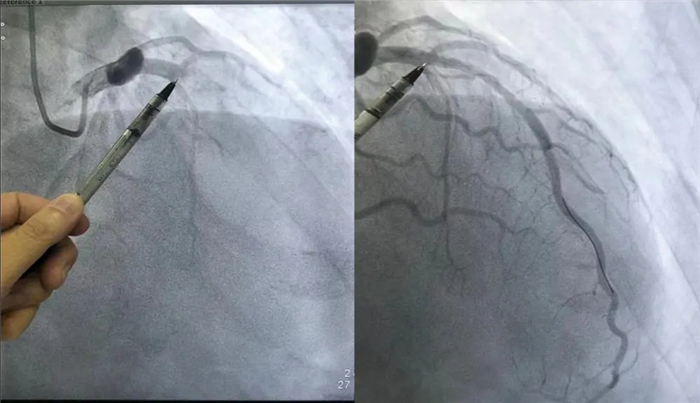

冠狀動脈造影,術(shù)前術(shù)后對比圖

科主任曾海、護(hù)士長明玲、導(dǎo)管室護(hù)士長吳鳳麗,帶領(lǐng)團(tuán)隊精誠協(xié)作。他們及時將患者送入導(dǎo)管室行冠狀動脈造影,手術(shù)發(fā)現(xiàn)冠狀動脈前降支急性閉塞,前向血流“0”級;當(dāng)即在冠狀動脈腔內(nèi)注入尿激酶原、欣維寧反復(fù)交替行溶栓治療,冠狀動脈腔內(nèi)反復(fù)多次行抽吸血栓術(shù),抽出大量紅色血栓塊,冠狀動脈腔內(nèi)血流恢復(fù)灌注,前向血流3級;手術(shù)成功挽救了患者生命,患者生命體征平穩(wěn)安全返回病房。